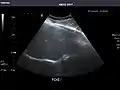

Liver

Liver: Diffusely homogeneous and normal in echogenicity. No focal mass or contour nodularity. No intrahepatic biliary ductal dilatation.